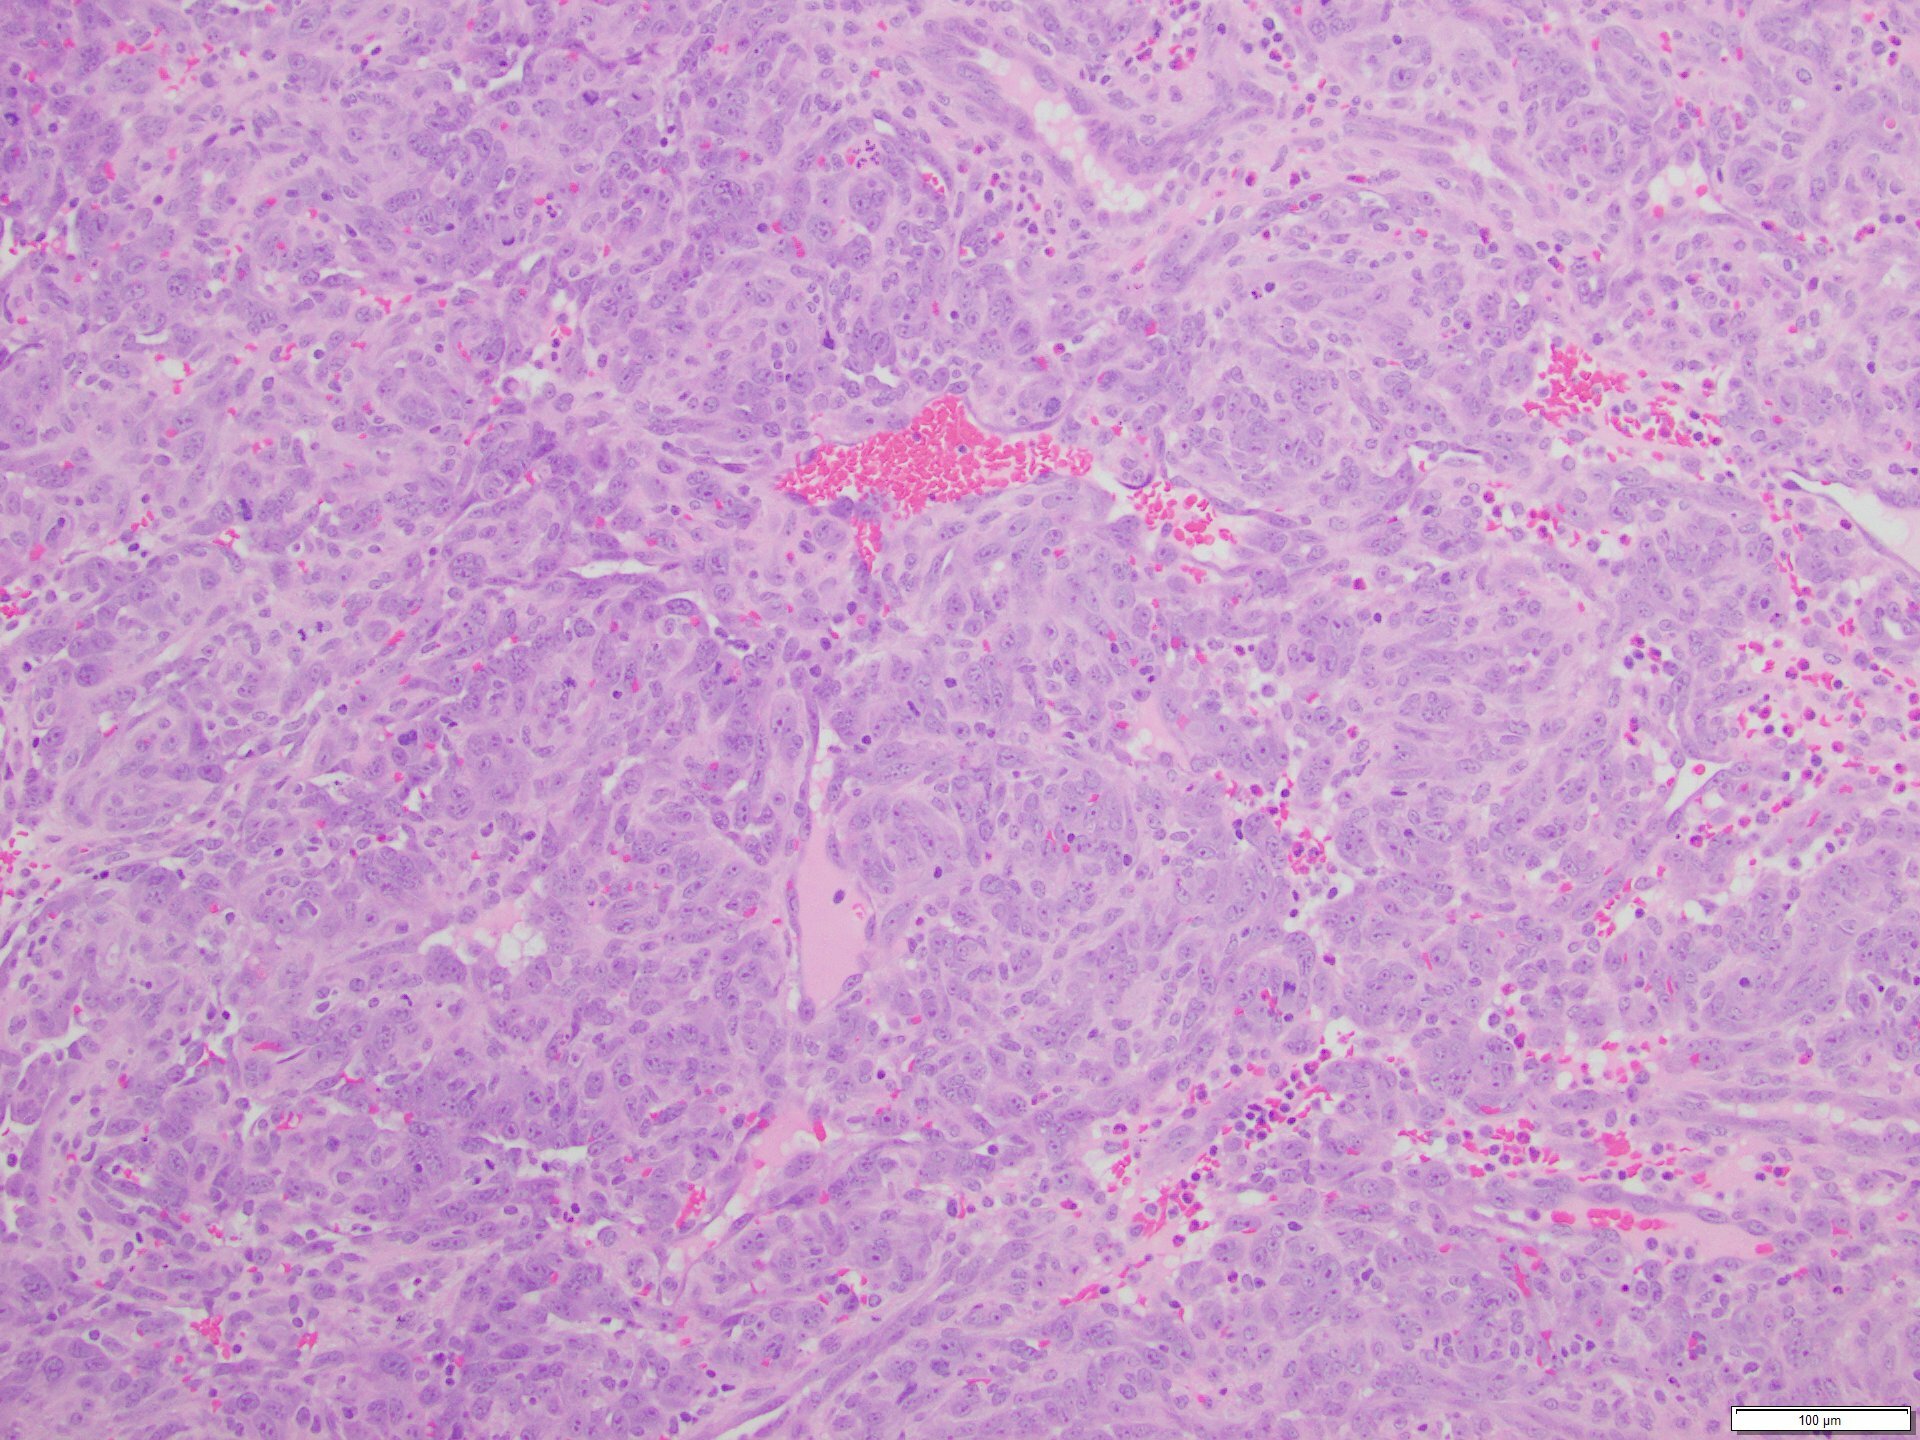

The skin lesion was completely excised and sent to pathology for diagnosis (Figures 1-3). The lesion is hypercellular with an infiltrative, predominantly solid, growth pattern in the dermis and subcutaneous tissue. It is highly vascular and has complex anastomosing and poorly formed vascular channels. The tumor cells are large, pleomorphic, have vesicular chromatin, and prominent nucleoli. There are frequent mitoses and extravasated red blood cells throughout. Immunohistochemistry shows the tumor cells are diffusely positive for ERG (Figure 4) and c-MYC (Figure 5) while negative for pan-cytokeratin (Figure 6) and GATA3. Subsequently, the patient underwent a left total mastectomy.